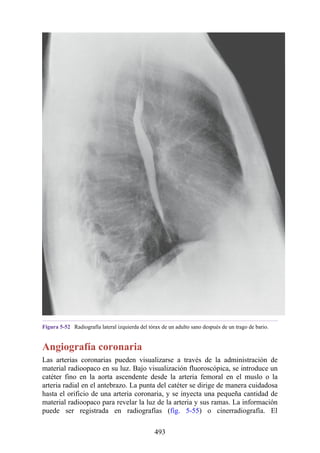

hombro. Debido a esta relación, estos cuatro músculos se conocen como

“manguito de los rotadores”. El manguito desempeña un papel muy importante

en la estabilización de la articulación glenohumeral (hombro). El tono de estos

músculos ayuda a fijar la cabeza del húmero en la cavidad glenoidea de la